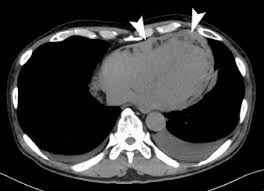

Solitary Fibrous Mediastinal Tumor With Coronary Vascular Supply An Unusual Case The Journal Of Thoracic And Cardiovascular Surgery

Solitary Fibrous Mediastinal Tumor With Coronary Vascular Supply An Unusual Case The Journal Of Thoracic And Cardiovascular Surgery from els-jbs-prod-cdn.jbs.elsevierhealth.com